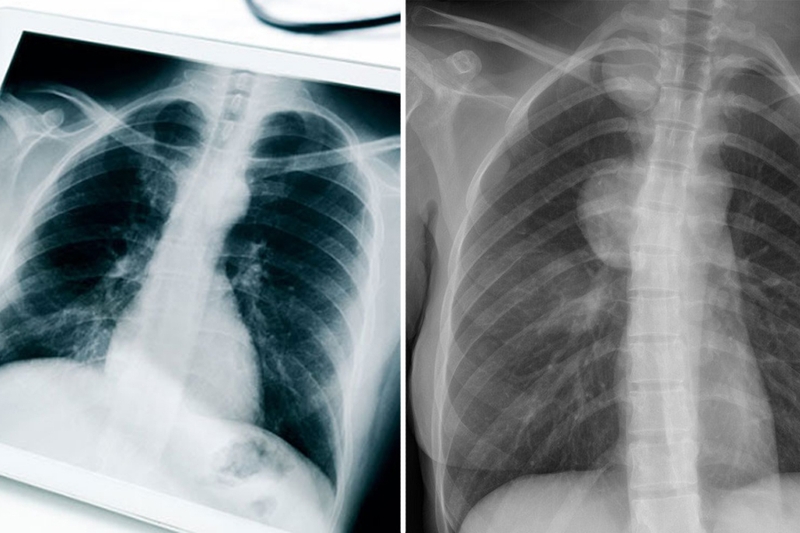

U trung thất là sự xuất hiện của khối u hoặc tổn thương trong vùng trung thất - khu vực nằm ở trung tâm lồng ngực, giữa hai lá phổi. Vùng này chứa nhiều cơ quan quan trọng như tim, thực quản, khí quản, mạch máu lớn, dây thần kinh và tuyến ức. Dựa trên vị trí giải phẫu, trung thất được chia thành ba phần chính: Trung thất trước, trung thất giữa và trung thất sau.

U trung thất ác tính là một dạng ung thư hiếm gặp nhưng có mức độ nguy hiểm cao do nằm ở vị trí trung tâm của lồng ngực, gần nhiều cơ quan quan trọng như tim và phổi. Tiên lượng sống của bệnh nhân mắc u trung thất ác tính phụ thuộc vào nhiều yếu tố như loại u, giai đoạn phát hiện và phương pháp điều trị. Vậy u trung thất ác tính sống được bao lâu và những yếu tố nào quyết định đến tiên lượng của bệnh nhân?